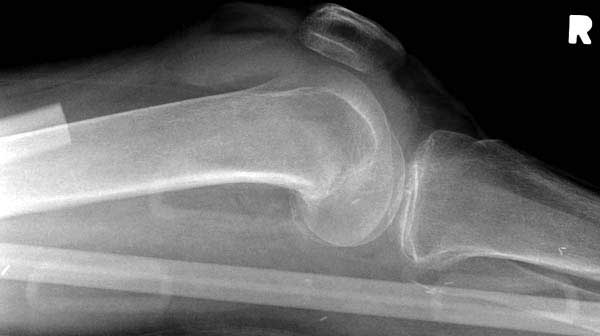

Обычно после чрезвертельных переломов, за исключением молодых, у пожилых остается нестабильность при движении. Часто падают и после 3х мес. в результате падения обнаружен перипротезный перелом (22-23), который зафиксирован Синтез пластиной.